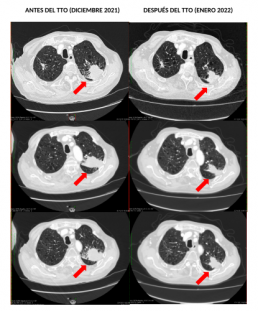

Vitamina C para aliviar los efectos secundarios del tratamiento contra el cáncer

Uno de los principales objetivos de INMOA no es solo tratar y curar los…